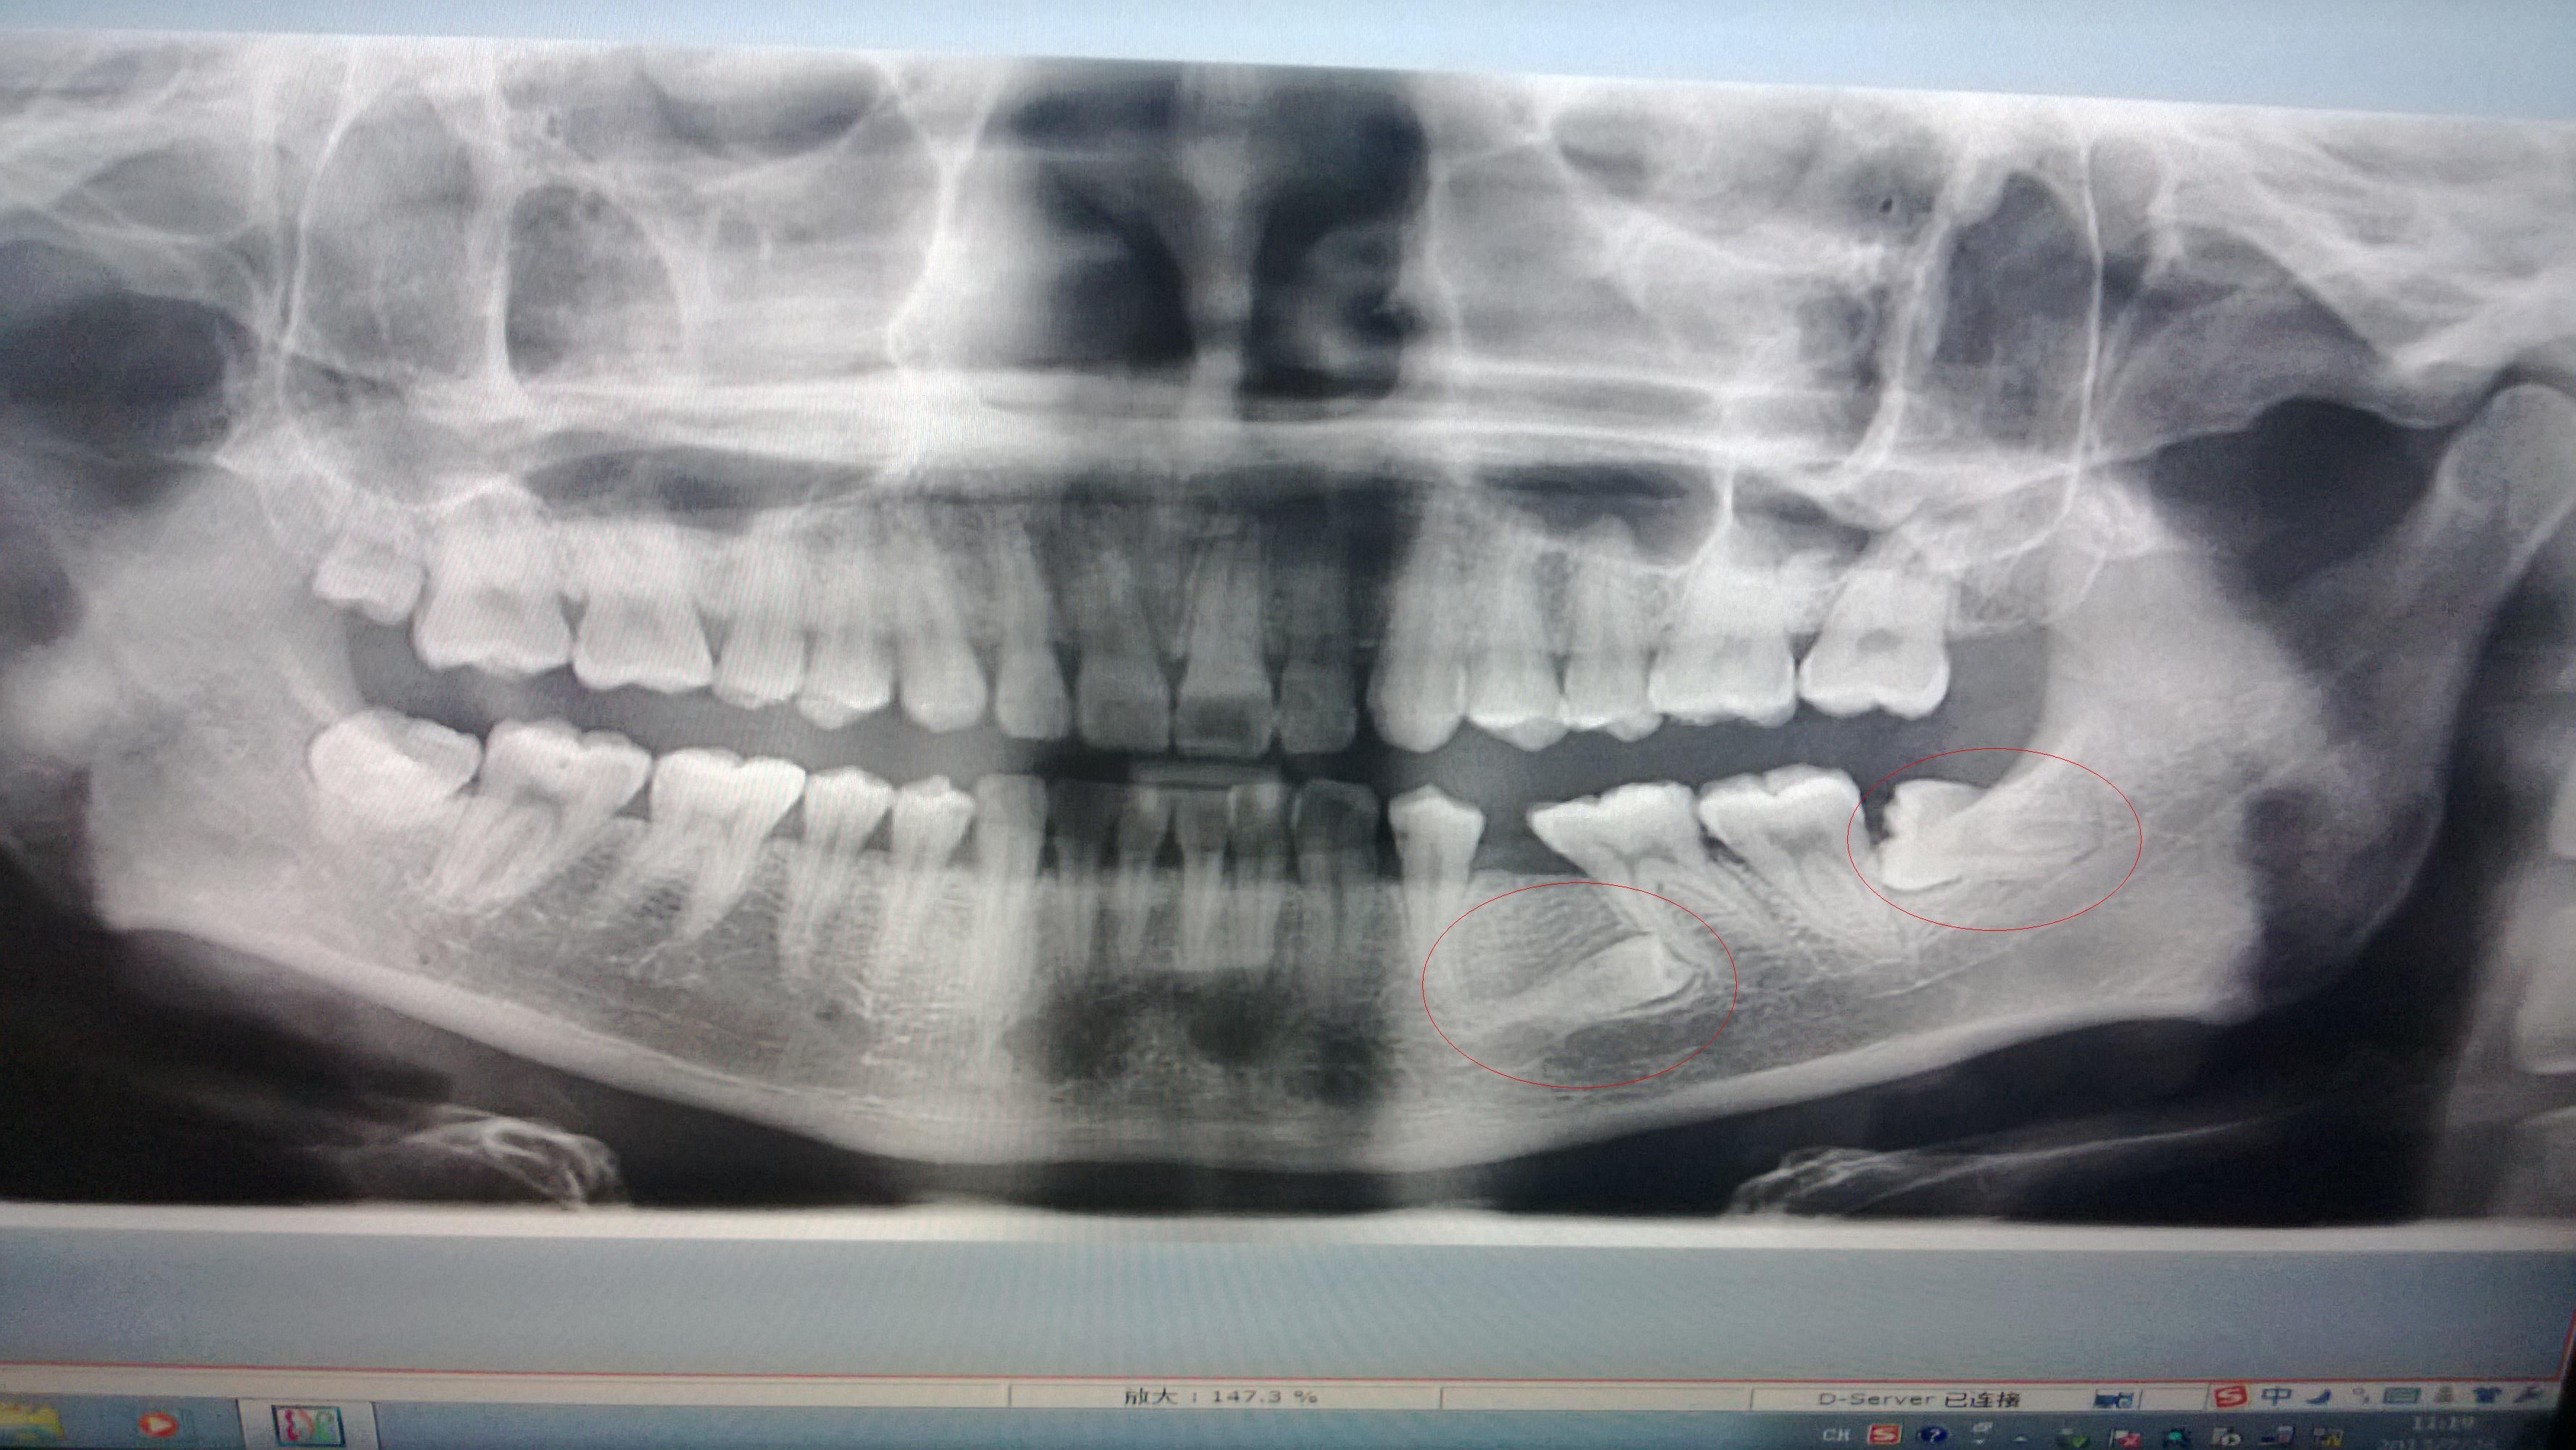

我的下牙齿,有两颗牙横着长在牙龈里了,有什么办法可以处理这个问题啊?种牙? 还是补牙啊? 情况如下:本人今年24岁,男,刚开始里面的大牙掉了之后,医生说我没有牙胚,结果最近才发现,那颗牙横着长在里面了。。。应该长了有10年了。最好的处理方式是什么啊?谢谢啦

最里面的牙齿(智齿)没得说 肯定得拔掉 你前面那个牙齿可以考虑保留.因为看了片子 5的牙冠是和6的近中根有重叠的,如果强制性的切开拔除,很可能会伤及到6的牙根,导致以后6也得做根治,所以建议保留 修复的话,如果没有拍摄牙齿CT,这样的牙齿就不要做种植了, 可能你种牙之后就种在你的牙齿上了. 拍摄完C...T之后可看到一个呈现立体样的图片.知道牙齿的三维方向,位置, 如果刚好避开了种植位置,那么还是可以做种植的, 如果确定在种植位置上!那么只能选用别的修复方法了!

左下5如果不影响什么就不用管它,如果发生疼痛就去权威口腔医院切开拔出,左下8必须拔出。左下5如果不痛,可以进行矫正,然后镶牙。